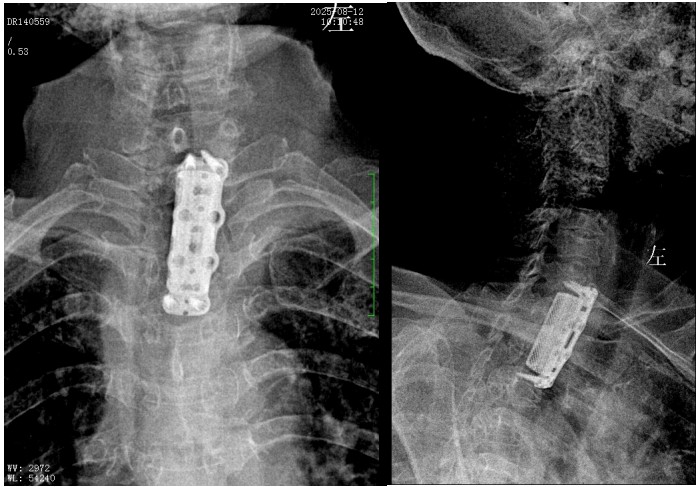

錢(qián)軍博士組織團(tuán)隊(duì)進(jìn)行了詳盡的術(shù)前討論,充分的術(shù)前準(zhǔn)備后,于8月10日為患者實(shí)施了“前路病灶清除、人工椎體植入、植骨融合內(nèi)固定術(shù)”。順利完成了徹底清除病灶,椎管減壓解除脊髓壓迫,矯正后凸畸形,重建脊柱穩(wěn)定性的手術(shù)目標(biāo)。